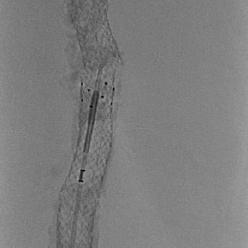

• Unique peripheral solution for difficult lower extremities occlusions including BTK and in-stent restenosis

• Considered the “Swiss Army Knife” for CTO’s, GoBack can be used for intraluminal crossing and guidewire support

• Unique needle design / shape, axial protrusion or lateral protrusion selector, with excellent pushability and torqueability

• 4 different needle protrusion lengths/shapes

• Needle protrusion length selector on handle